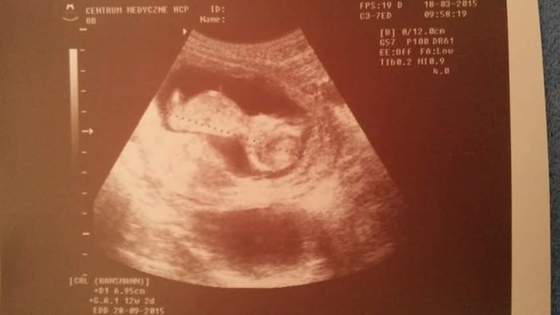

. No nie powiem byłam mega zaskoczona i zszokowana :/ Mówię do lekarza że może się jeszcze zmieni, a On na to że już się raczej nie zmieni, nie skróci się i tak z Dominiki zrobił się Michał (nie Piotr)...